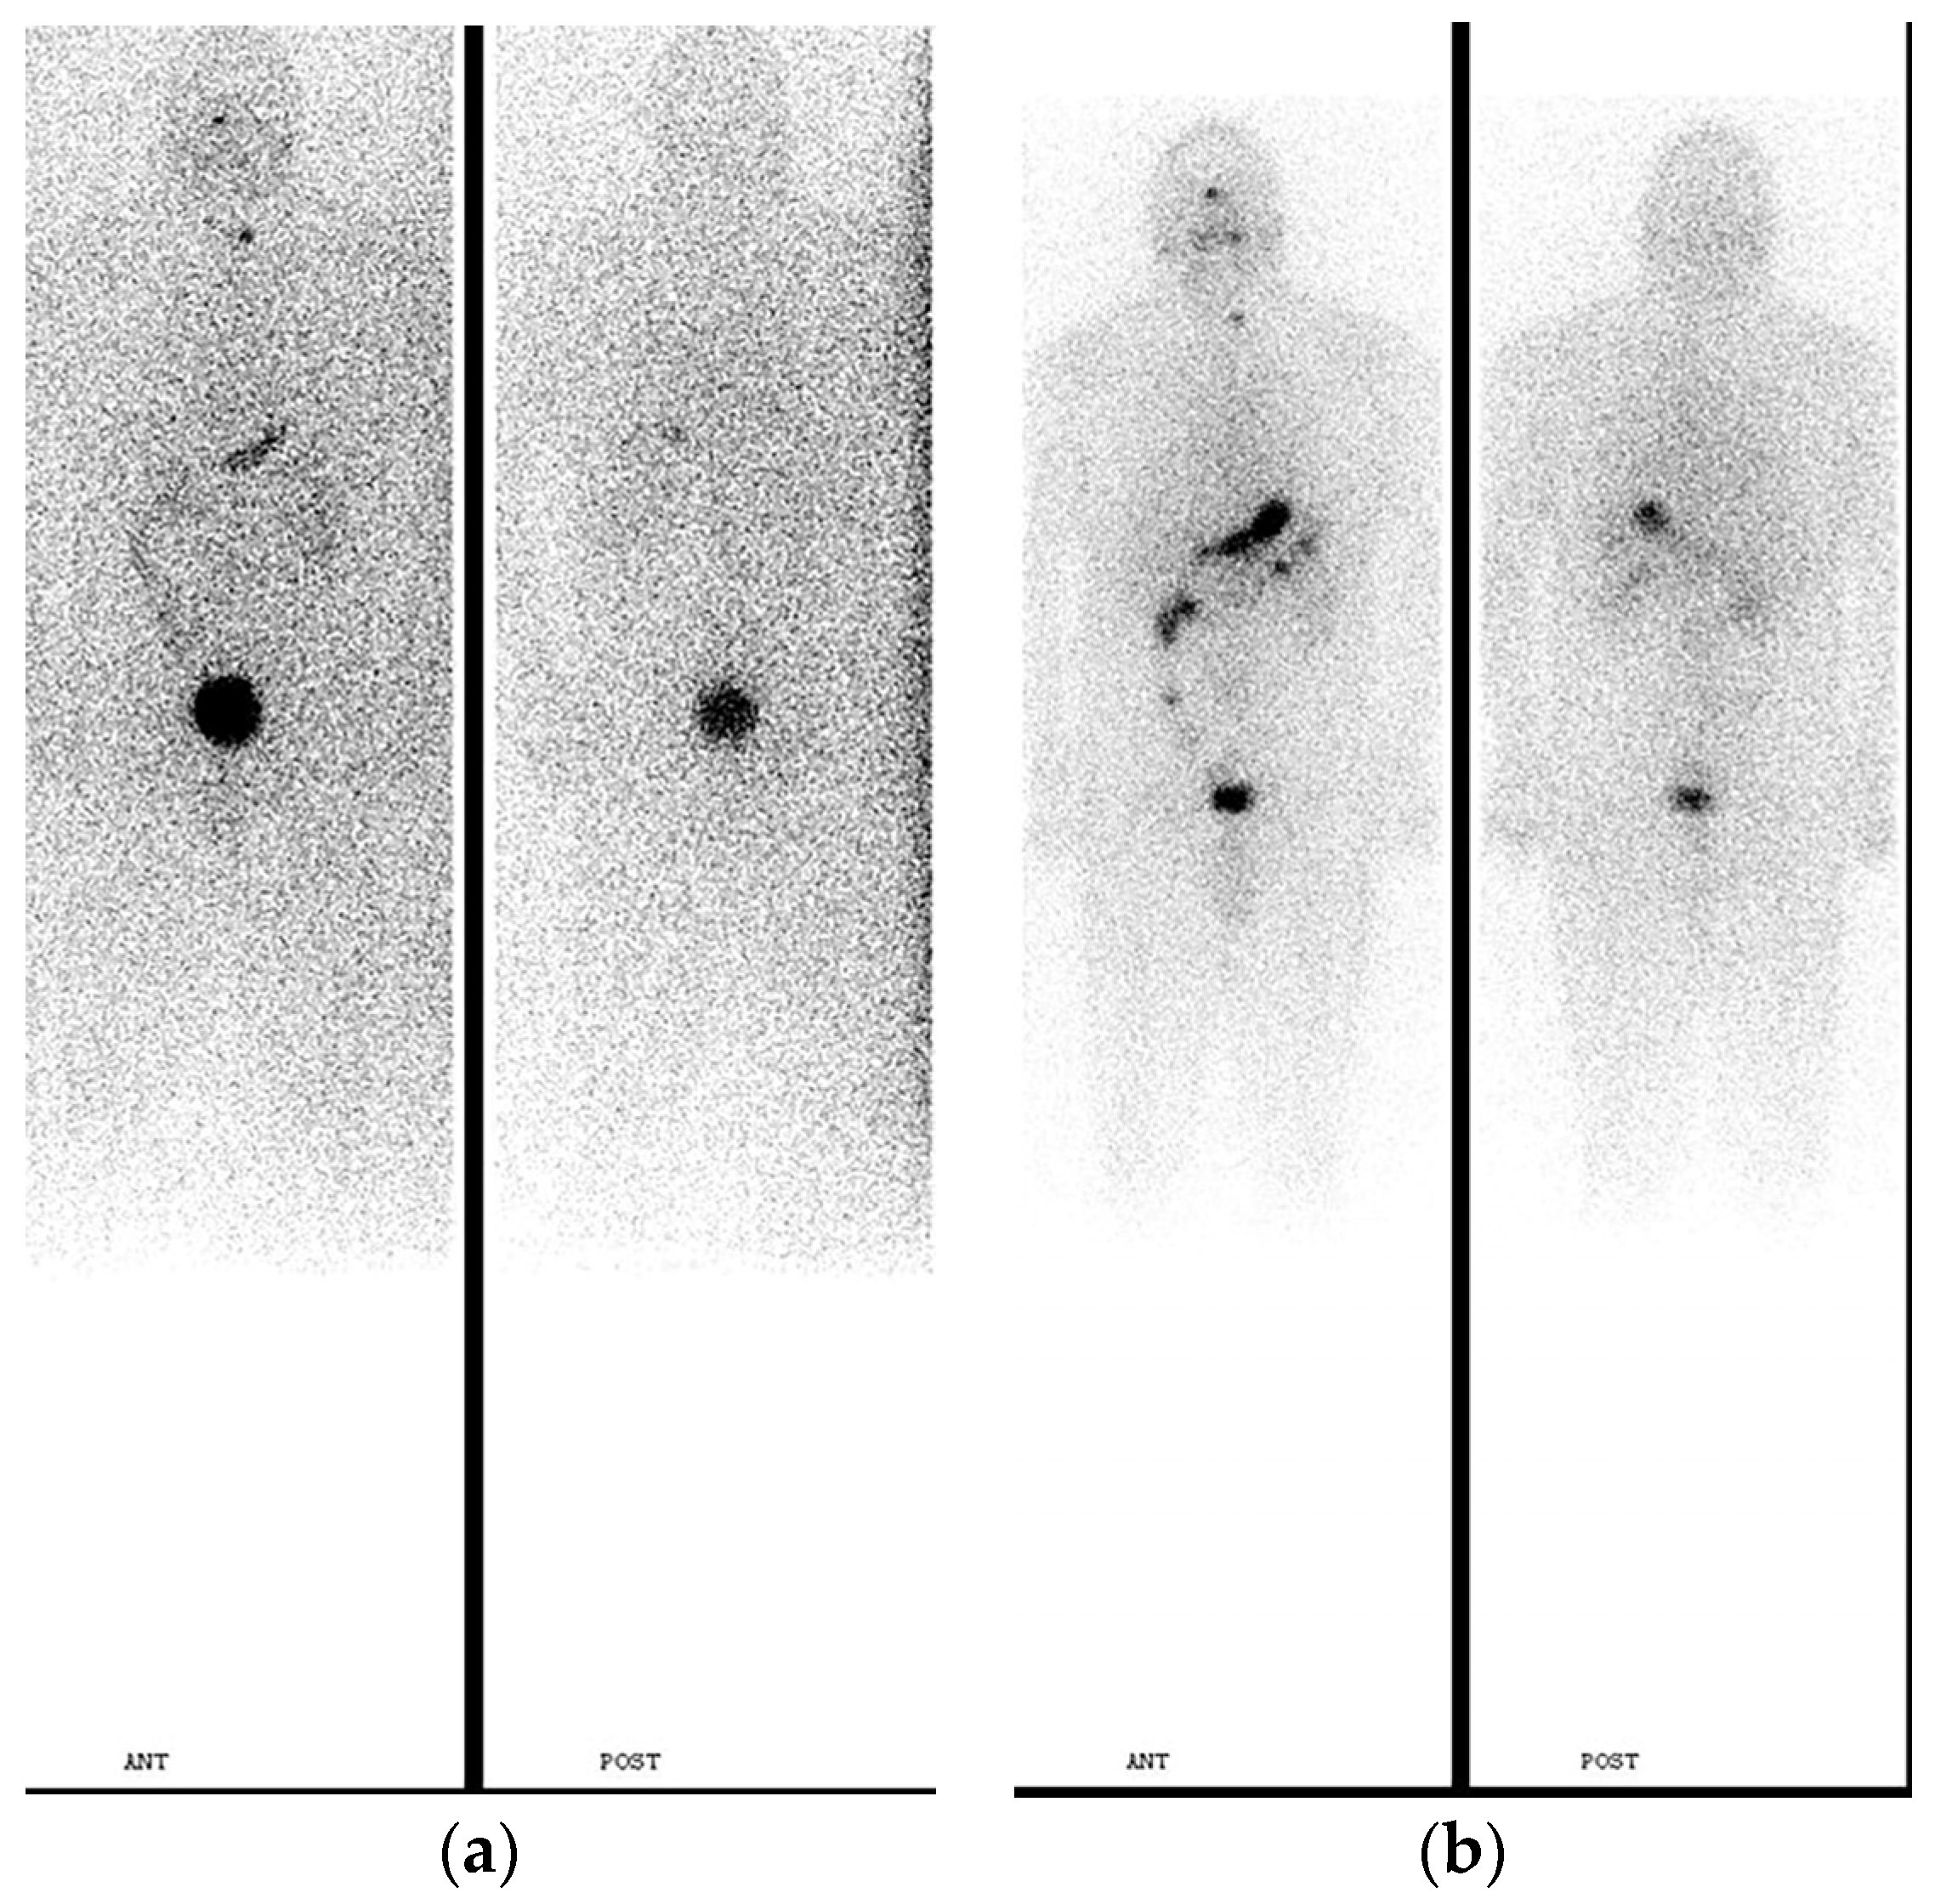

2. Pre-Treatment Whole-Body Imaging

3. Post-Treatment Whole-Body Imaging